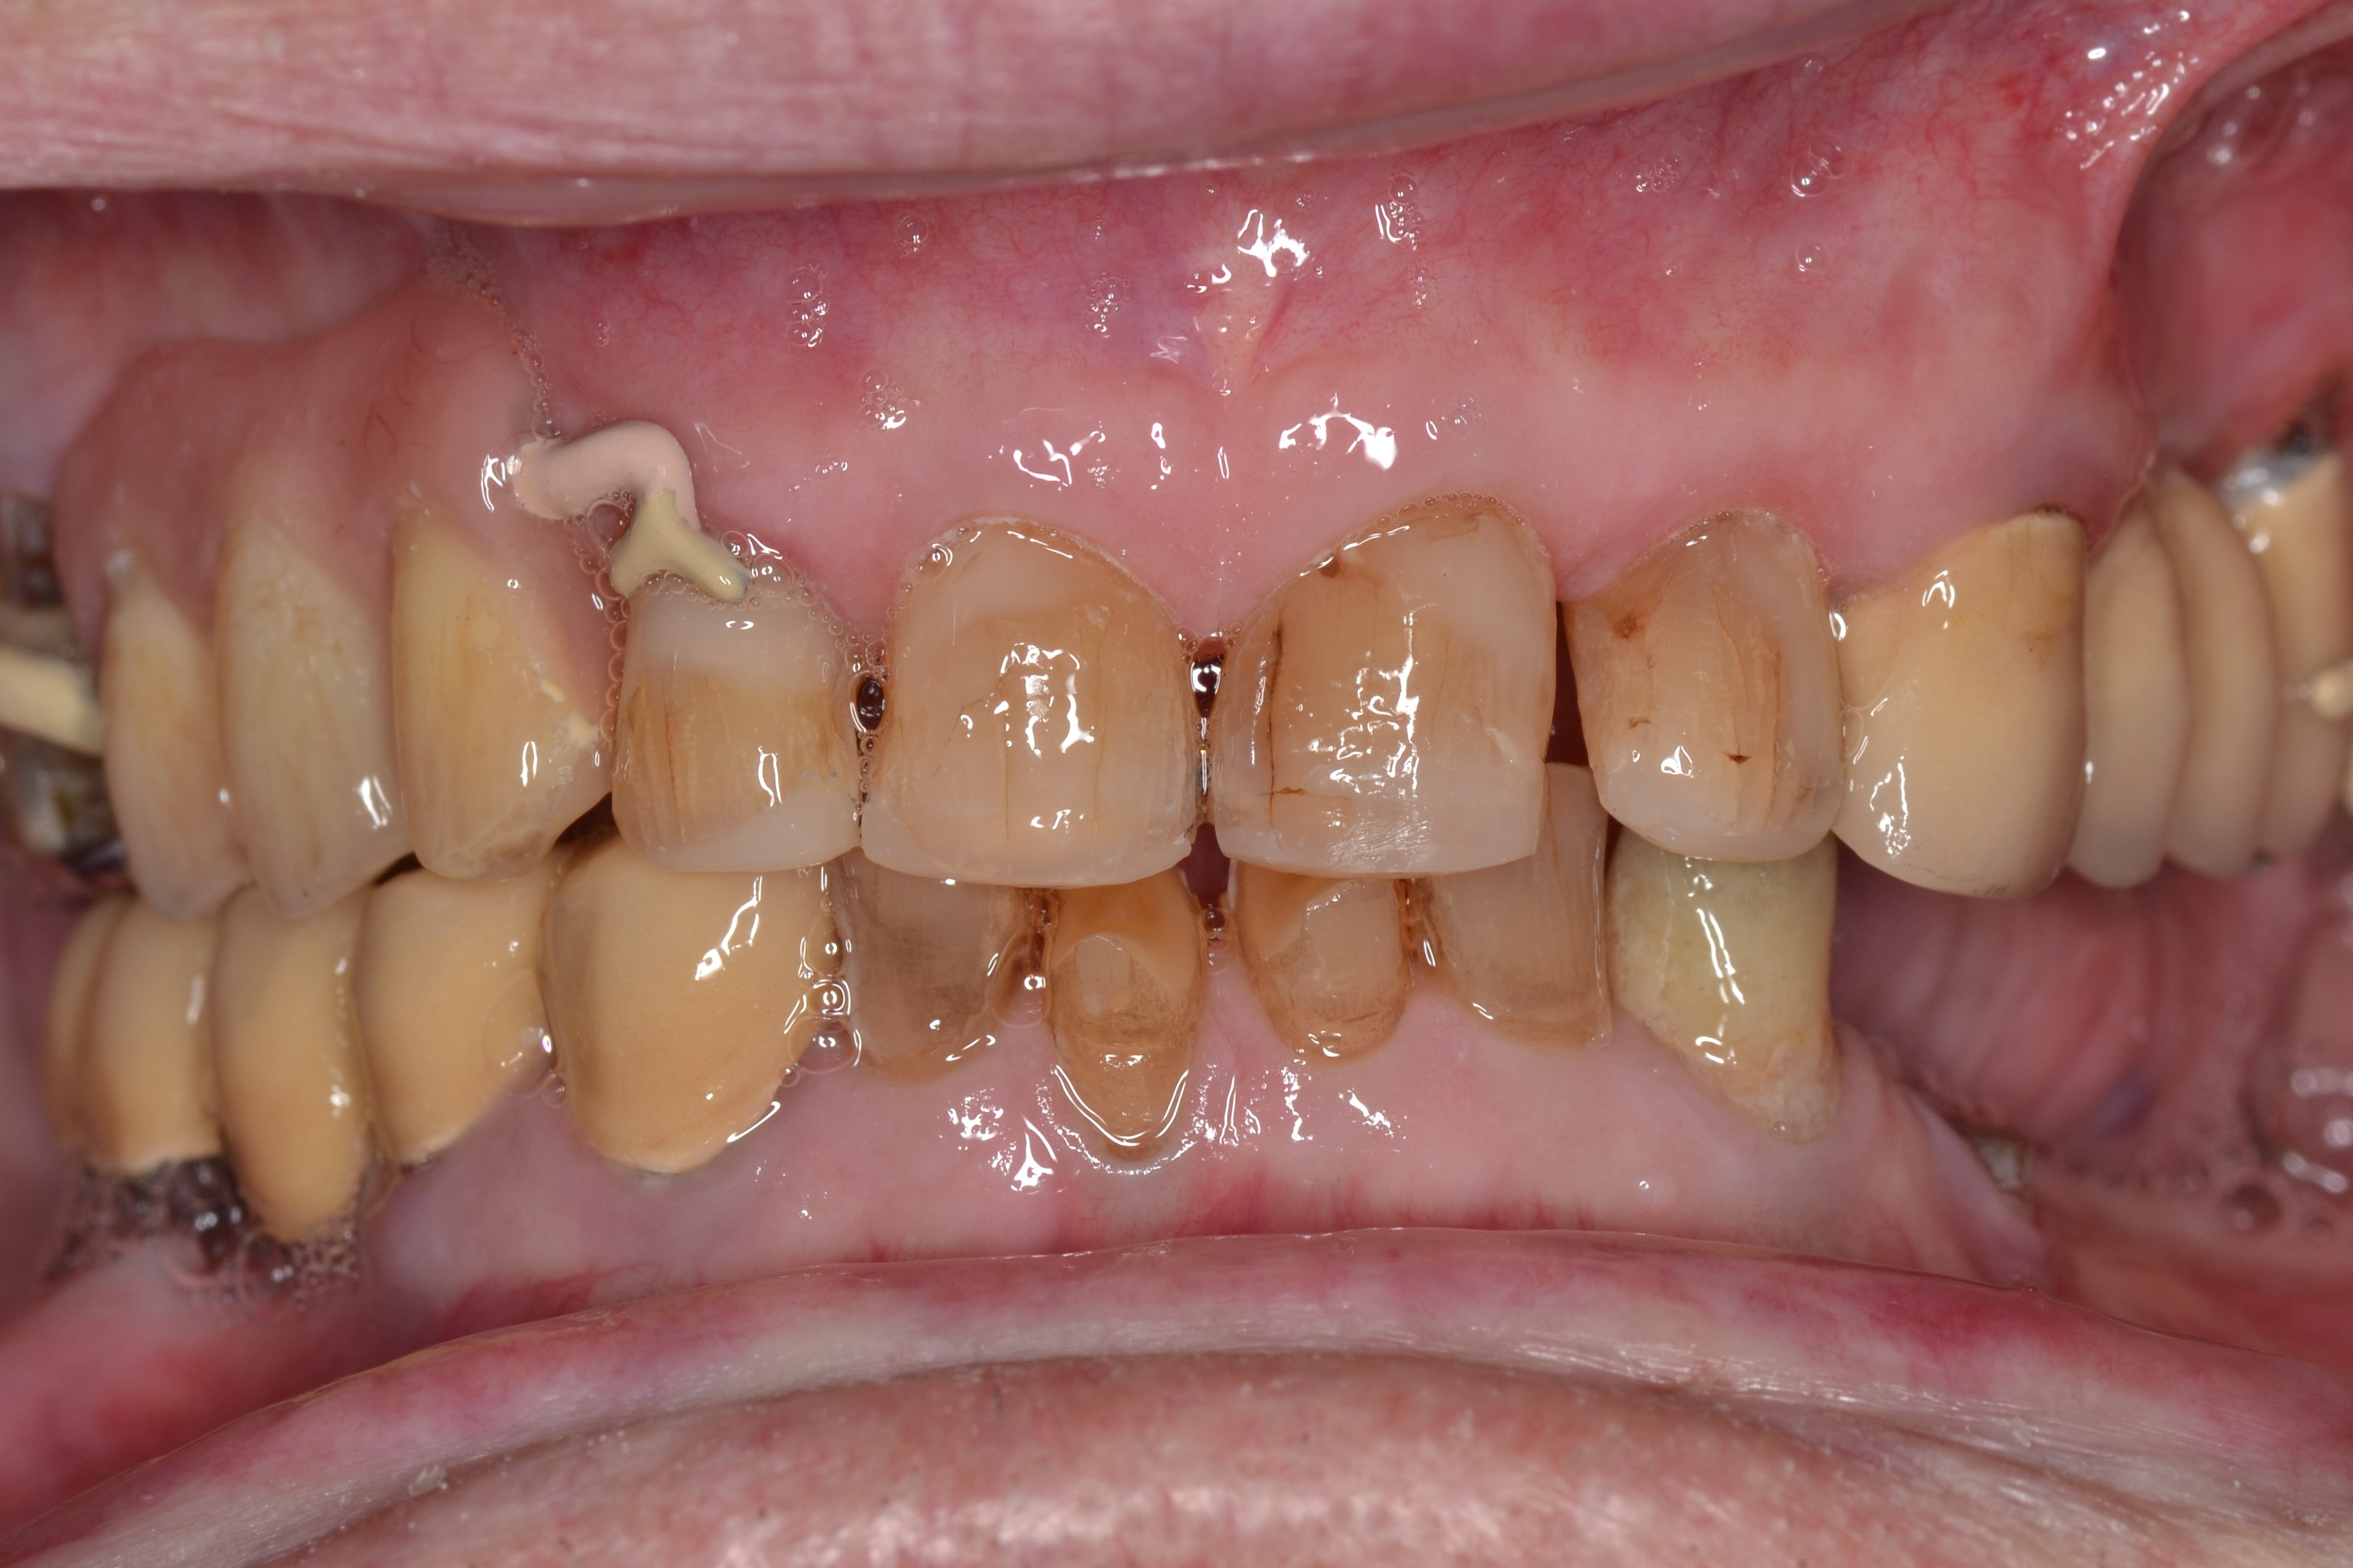

This 60-years old patient was missing a few teeth in his upper right jaw.The remaining teeth were mobile and tender when eating.

We extracted the remaining upper teeth and made him a full acrylic denture.